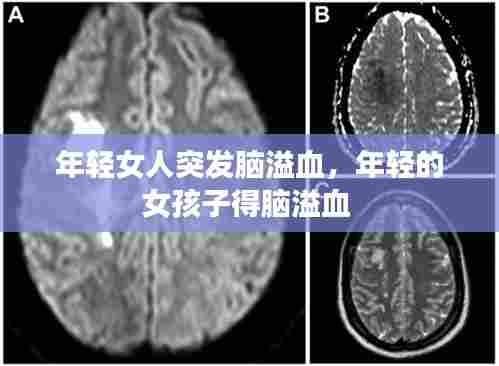

生命的挣扎:与时间赛跑的抢救

脑溢血是一种严重的脑部疾病,如果不及时治疗,可能导致生命危险。在医院里,医生迅速对李婷进行了CT检查,确诊为脑溢血。随后,她被紧急送往手术室,接受开颅手术。手术过程中,医生们争分夺秒,试图挽救李婷的生命。